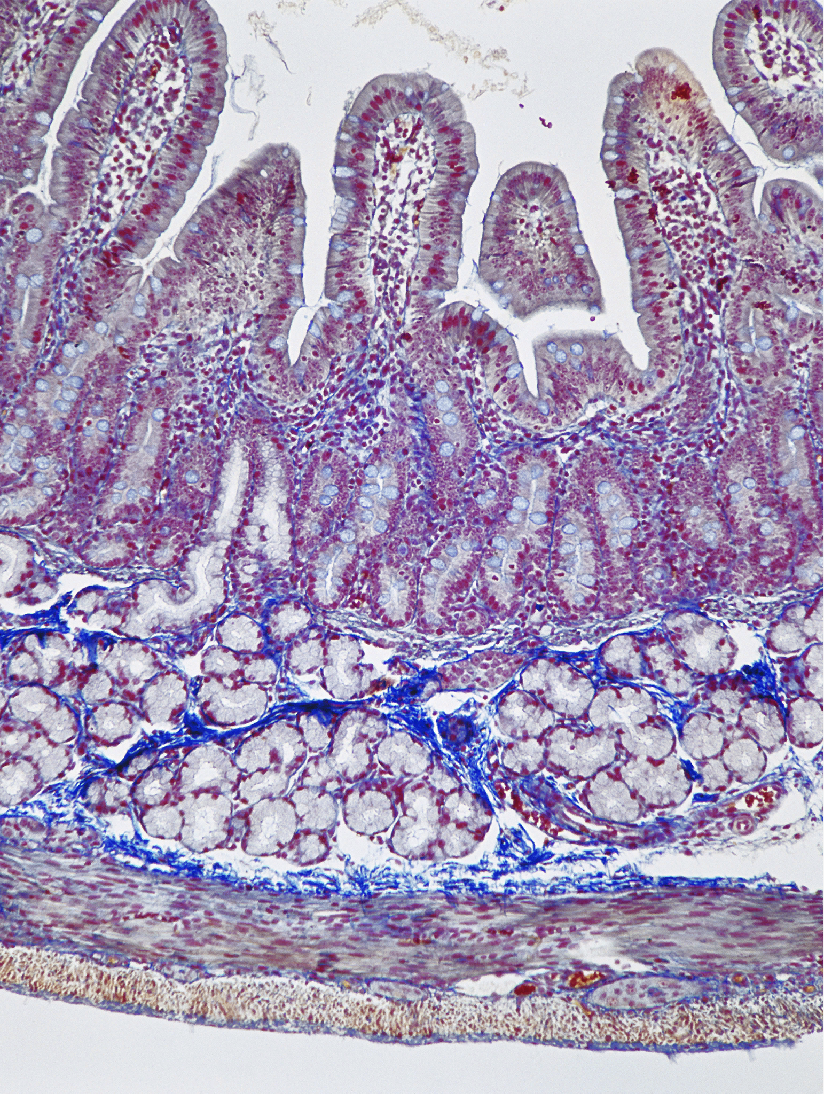

List the layers of the stomach

Mucosa- simple columnar epithelium & mucous cells

(Contains Gastric pits and Gastric glands)